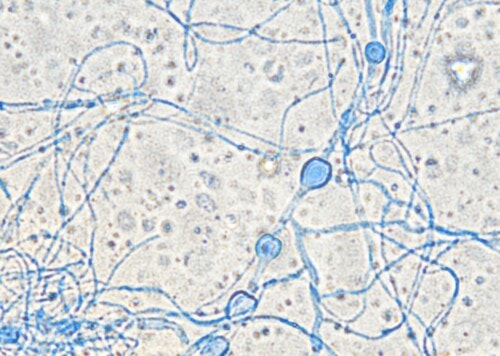

Des biopsies cutanées sont de nouveau réalisées pour une deuxième tentative de culture fongique sur milieux SC et SCA à 27°C et 37°C, révélant, sur milieu SC à 27°C uniquement, la présence de nombreuses colonies d’un champignon filamenteux non identifié (photo 8).

Photo 8 : examen microscopique d’un calque coloré obtenu à partir du prélèvement reçu par le laboratoire de mycologie : notez la présence de nombreuses colonies d’un champignon filamenteux à ce stade non identifié

Un séquençage PCR conduit finalement à l’identification d’un champignon du genre Penicillium de la section Ramosum et plus particulièrement d’un représentant du groupe Raistrickiorum. Le traitement à base de kétoconazole est repris mais est associé à une mauvaise tolérance (vomissements et abattement) et ne permet pas d’amélioration clinique après 1 mois de prise en charge. Il est alors remplacé par un traitement à base d’itraconazole (5mg/kg/j), permettant une résolution des lésions en 3 mois (photos 9 et 10). Un mois plus tard, suite à une fugue dans la forêt, de nouvelles lésions sévèrement ulcératives et nécrotiques se sont rapidement développées sans évolution favorable (photo 11), menant à l’euthanasie de la patiente 3 mois après la fin du traitement à base d’itraconazole. L’autopsie a été proposée mais refusée par les propriétaires.